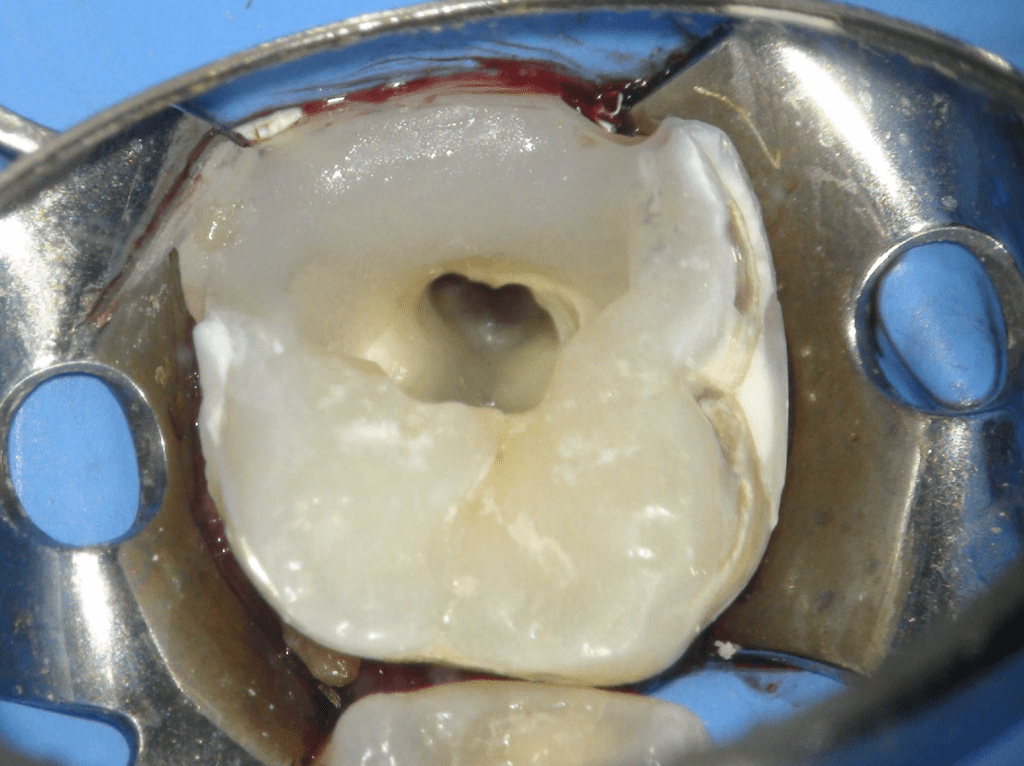

Pulpotomía biodentine + reco preendio